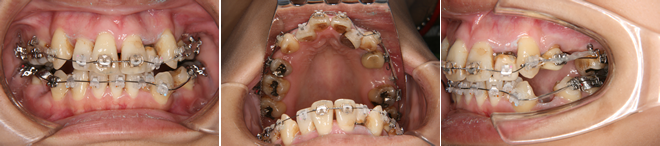

| 主訴 | 上の前歯が出ている、下の前歯がデコボコ |

| 年齢・性別 | 26歳 / 女性 |

| 治療方針 | 顎関節に少し問題があるAngleⅠ級上下顎前突。患者の希望もあり、できるだけ前歯を後退して口元の突出感の改善を行う。 |

| 抜歯部位 | 小臼歯4本抜歯 |

| 使用装置 | ホールディングアーチ、マルチブラケット装置 |

| 治療期間 | 26か月 |

| リテーナー | 上顎インビジブル、下顎スプリングリテーナー |

| 費用 | 825,000円(税別) |